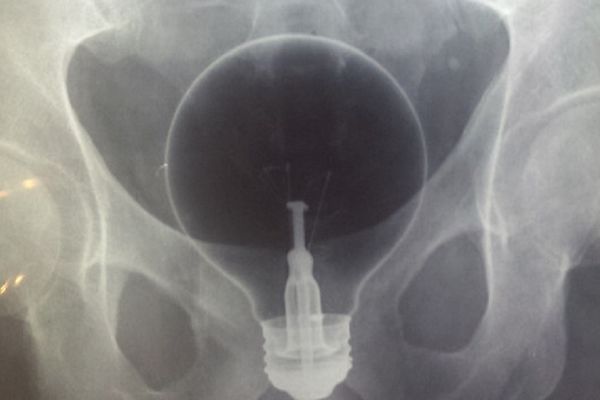

TOTALNO UVRNUTI SLUČAJEVI

12 rendgenskih snimaka koji dokazuju da smo okruženi čudacima! (FOTO)